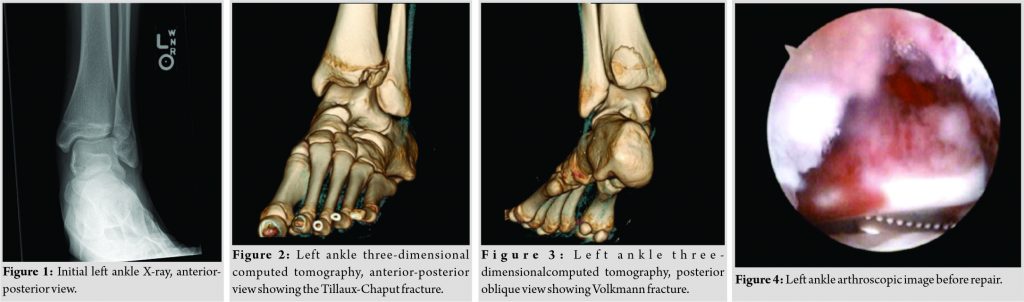

Our patient is a 16-year-old male with no medical history who presented to our emergency department from another institution after being tackled in a junior varsity football game. He experienced a significant blunt trauma to the abdomen resulting in a brief loss of consciousness. He felt immediate pain in his left ankle on awakening; however, he was able to bear weight briefly until the pain became too severe. On examination, he had a generalized swelling over both the medial and lateral aspects of the left ankle compared with the right. Ecchymosis was also present on the medial side of the left ankle. He displayed tenderness to palpation over the anterolateral portion of the left ankle only. Radiographs in the anterior-posterior (Fig. 1), lateral, and oblique views revealed a Salter-Harris type IV fracture of the distal left tibia involving the posterior tibial metaphysis and the anterolateral aspect of the tibial epiphysis. The epiphyseal fragment was displaced proximally, anteriorly, and laterally, with a 2.5 mm step-off at the articular surface seen on the lateral view. Due to high suspicion for a Tillaux fracture and inadequate evidence on plain radiographs, a computed tomography (CT) scan of the left ankle without intravenous contrast was taken. This study revealed an avulsion fracture of the anterolateral tibial epiphysis that is laterally and anteriorly displaced in addition to the non-displaced fracture of the posterior malleolus involving the metaphysis and extending into the tibial plafond with no significant step-off (Fig. 2 and 3).